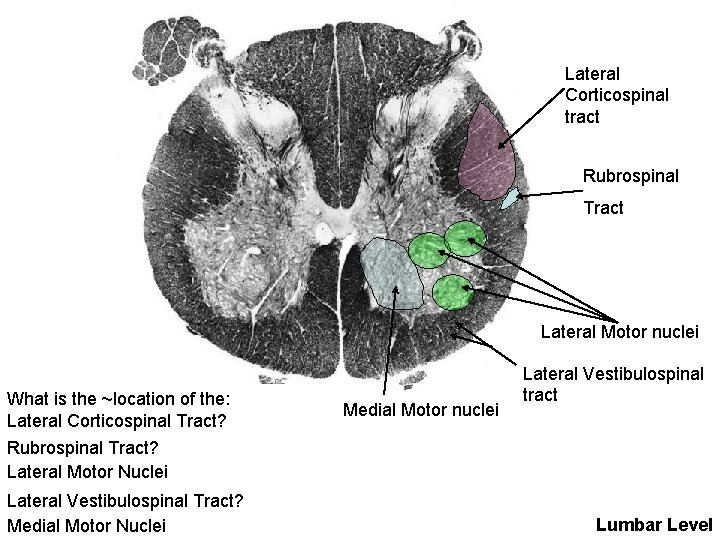

Lateral Corticospinal tract Rubrospinal Tract Lateral Motor nuclei What is the ~location of the: Lateral Corticospinal Tract? Medial Motor nuclei Lateral Vestibulospinal tract Rubrospinal Tract? Lateral Motor Nuclei Lateral Vestibulospinal Tract? Medial Motor Nuclei Lumbar Level